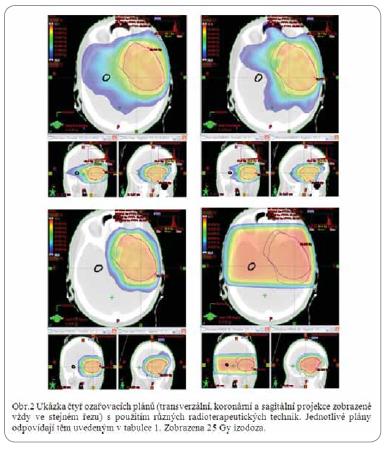

Na našem modelovém příkladu jsme ověřili proveditelnost tohoto postupu se současným dodržením předepsaných dávek záření do oblasti cílového objemu (tab. 1, obr. 2). U vybraných pacientů se může hippocampus řadit k ostatním tradičním rizikovým strukturám (optické nervy, chiasma nebo mozkový kmen).

Plán 1 |

Plán 2 |

Plán 3 |

Plán 4 |

PTV2 Dmean [Gy] |

59,91 |

59,93 |

59,90 |

60,11 |

Hippocampus kontralat Dmean [Gy] |

35,14 |

19,62 |

16,38 |

56,74 |

Tab.1 Hodnoty Dmean [Gy] pro cílový objem a kontralaterální hippocampus při testování různých radioterapeutických technik